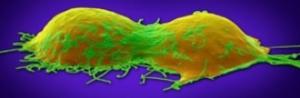

CANCER de l’OVAIRE : Découverte d’un gène régulateur majeur

Actualité publiée le 21/04/2022CANCER de l’OVAIRE : Comprendre l’interaction cruciale entre le sang et la tumeur

Actualité publiée le 27/08/2021

Actualité publiée le 12/08/2019CANCER de l’OVAIRE : Pousser les cellules cancéreuses à la sénescence

Actualité publiée le 29/07/2019